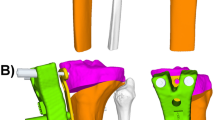

Following the final checks by the senior author and surgeon, the simulated osteotomy and correction were made using the Bodycad Osteotomy software. The WBL (weight-bearing line) correction to 55% of the tibial plateau width was chosen. An opening of 10.21 mm was calculated by the software to obtain this particular correction. The resulting patient’s lower limb alignment was calculated to be a tibiofemoral valgus alignment of 1.69° and a MPTA of 91.86°, with no change of the tibial slope (Figs. 3, 4). The hinge axis was planned to be at an ideal position of 15 mm from the lateral plateau and 10 mm from the lateral cortex. A biplane cut was proposed due to the tibial tuberosity that was in the way of the osteotomy cutting plane. The cut was positioned just below the ACL screw (Fig. 5). Approval of the pre-operative planning was done prior to manufacturing the patient-specific surgical guide and plate (Figs. 6, 7 and 8).

The patient was placed under general anesthesia. An arthroscopy of the knee was made prior to the osteotomy; a partial medial meniscectomy and chondroplasty of the medial compartment were performed. The ACL graft was intact. Next, attention was turned to the proximal tibia for exposure of the OWHTO site. A 7-cm longitudinal skin incision at the anteromedial aspect of the proximal tibia, between the patellar tendon and the medial collateral ligament, was made in standard fashion. Prior to placing the cutting guide, the 3D-printed sterile bone model was used to confirm the position and contact region of the surgical guide over the bone. Temporary fixation screws were used to fasten the guide in place (Fig. 9). Two drilling towers were locked into the surgical guide (Fig. 10). Using a pre-calibrated drill (with depth control), multiple holes cortical perforations were made at the osteotomy location. The drilling towers were then removed, so that the surgeon had access to a slot to insert a calibrated osteotome to finish the cut. The anterior part of the surgical guide was then clipped off and removed, leaving only the posterior part over the patient’s bone. The biplane vertical cut behind the patellar tendon was finished using an osteotome. A fluoroscopy shot was made to confirm the completion of the cut. The calibrated bone spreader was inserted into the anchors (posterior section of the guide which was left in place) (Fig. 11). Using the bone spreader, the osteotomy was slowly distracted with precise control. The osteotomy site was spread until it reached the planned correction, then slightly overcorrected to 11 mm to allow for placement of void filler and the plate (Fig. 12). Since the design of the plate was overlapping with the anchor boxes, a lamina spreader and a 3D-printed validator block were inserted into the osteotomy to be able to remove the bone spreader and the anchors boxes (Fig. 13). The pre-drill guide was inserted over the bone and used to pre-drill the plate’s screw hole using a depth-controlled drill. The plate was then inserted on the bone, and temporary fixation pins were used to maintain alignment of the plate with the pre-drilled holes. Only the four proximal screw holes and the first distal screw holes were pre-drilled using this technique. The remaining screw holes were drilled through a drill tower that locked into the plate. A patient-specific sterile planning card (anodized aluminum) was provided with the plate and screws to confirm with the surgeon which screws (type and length) were to be placed in each of the specific screw holes (Fig. 14). The screws were then inserted in the plate (Fig. 15) and seated flush (Fig. 16). A 7 mm synthetic beta-tricalcium phosphate graft (OSFerion Osteotomy Wedge, Arthrex, Naples, the USA) was used to fill the gap. Two fluoroscopy shots (frontal and lateral views) were taken to confirm the implant placement and screw positions (Fig. 17).